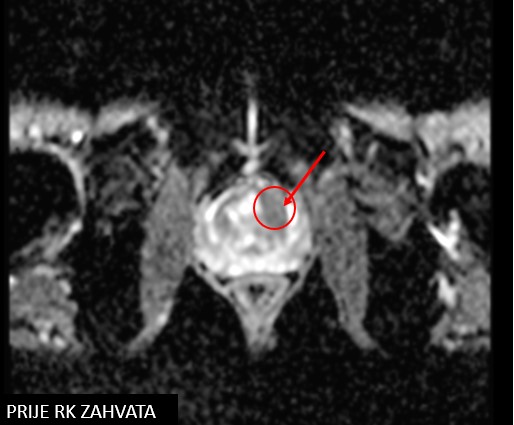

Npl prostatae, cT1c

Biopsio prostatae (10/2019)

PHD: Adenocarcinoma prostatae GS 3+4, 2/12 cilindara

iPSA 13

SABR npl. prostatae (04.02.-12.02.2020.)